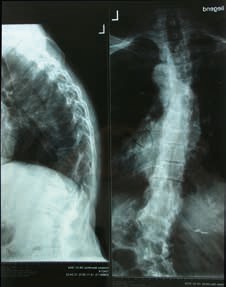

Die Behandlung von adoleszenten idiopathischen Skoliosen (AIS) im Bereich von circa 20 bis 45 Grad nach Cobb mit modernen Korsetten ist gängige Praxis. Vorzugsweise kommen Derotationskorsette nach Chêneau/Rigo zum Einsatz. In Europa gilt dies als Goldstandard. Die hohe Wirksamkeit der Korsetttherapie wurde 2013 in einer international beachteten Studie von Weinstein et al. 1 belegt. In den letzten Jahren ist die Problematik der adulten Skoliose durch die gestiegene Lebenserwartung deutlich relevanter geworden: Im Gegensatz zur adoleszenten Skoliose, bei der eine Verringerung der Krümmungswerte und eine korrekte Lenkung des Wirbelsäulenwachstums absolute Priorität haben, steht bei der konservativen Behandlung der adulten Skoliose die Entlastung der Verkrümmung und eine Wiederherstellung der lotrechten Wirbelsäulenstatik im Vordergrund. Ziel der Versorgung ist es, einen schmerzfreien Zustand zu erreichen (Abb. 1). Von einer adulten Skoliose spricht man definitionsgemäß nach vollständigem Wachstumsabschluss mit klinisch relevanter Manifestation, meist nach der vierten Lebensdekade.

Patienten mit adulter Skoliose leiden unter lumbalen Rückenschmerzen, oft schon bei kurzen Gehstrecken. Sie haben eine deutliche Fehlstatik mit drastischer Seitabweichung der Wirbelsäule und eine eingeschränkte pulmonale Kondition. Es kommt zu Fehlbelastungen der Rumpfmuskulatur und der unteren Extremität. Außerdem ist meistens die Statik in der sagittalen Ebene deutlich verändert und zeigt mit zunehmendem Fortschreiten der Skoliose ein nach vorn gebeugtes Gangbild, bis hin zur Kamptokormie, einer Haltungsanomalie in vorgebeugter Haltung 3. Die Prävalenz der adulten Skoliose wird mit mehr als 2,5 Prozent und deutlich darüber angegeben.